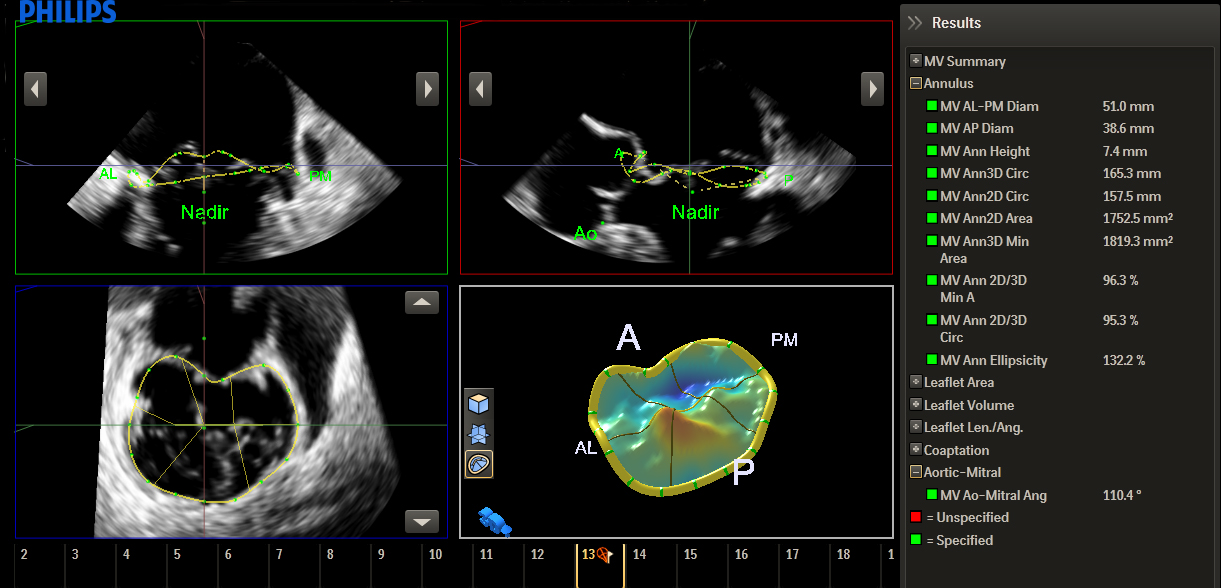

Функция интеллектуального определения анатомических структур изучает данные УЗИ пациента и применяет адаптивную интеллектуальную логику системы с использованием трехмерных анатомических моделей для создания более простых и воспроизводимых результатов. Инструменты интеллектуального определения анатомических структур, например HeartModel, используют усовершенствованное моделирование органов, формирование срезов изображений и надежный количественный анализ, помогая упростить проведение УЗИ, обеспечивая более высокую воспроизводимость, предоставляя при этом клиническую информацию нового уровня для решения экономических и клинических задач, возникающих в условиях современного медицинского учреждения.

Инструменты интеллектуального определения анатомических структур превращают изображения в ответы